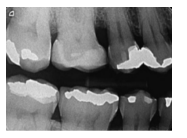

Assinale a alternativa que identifica o nome da técnica radiográfica da imagem ao lado.